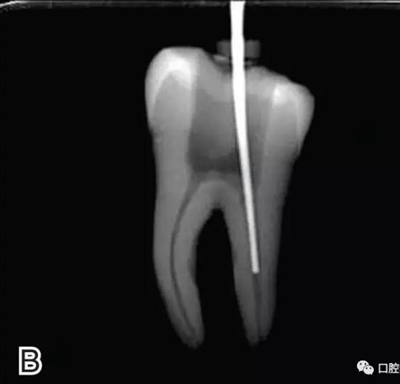

要求工作尖能自由到達(dá)距根尖4~5 mm(有學(xué)者提出3~4 mm)的位置并能輕微接觸根管壁,用橡皮片做好標(biāo)記(圖1)。

圖1 選擇攜熱器工作尖,A.試攜熱器尖 B.工作尖在根內(nèi)的位置